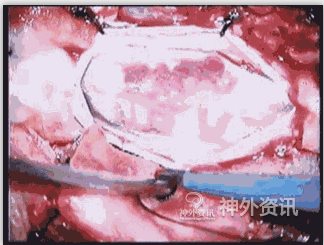

图9: G. 显微手术灼闭瘘口,动态录像。